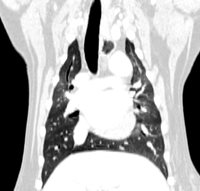

L'examen se déroule normalement en deux phases : une première phase d'acquisition d'images, dite sans préparation, suivie d'une deuxième phase, après injection d'un produit de contraste iodé par voie intraveineuse. Le produit de contraste permet de rehausser les structures vasculaires et certains tissus (en particulier les tumeurs). C'est la comparaison des deux séries d'images qui permet d'affiner le diagnostic tomodensitométrique.

Coupes Axiales : Thorax Caudal avant et après IV